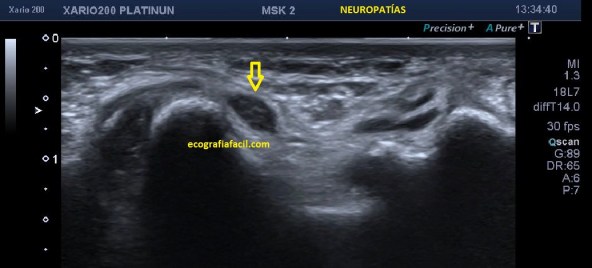

Neuropatías

Las neuropatías cambian el aspecto de la ecoarquitectura normal de nervio y lo aumentará de tamaño y lo volverá hipoecogénico (flecha amarilla), eventualmente pueden sufrir luxaciones como en este Vídeo de mi canal de Youtube.